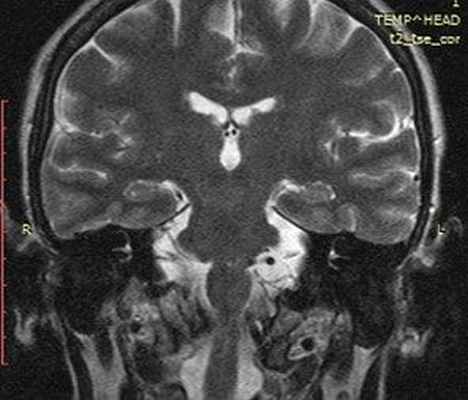

На корональной томограмме с обеих сторон хорошо видны тройничные нервы

Рис. 1. МРТ головного мозга в аксиальной и коронарной проекциях: отмечается близкое расположение петли базилярной, петли ветви верхней мозжечковой и передней нижней мозжечковой артерий к корешку левого лицевого нерва в зоне его выхода из вещества моста.